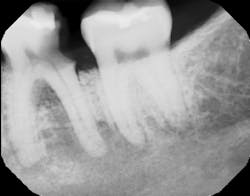

In summation, the best treatment for nerve injury continues to be prevention. If there is any doubt by the treating clinician as to the proximity of an odontogenic lesion to the nerve space (figure 4), a CT scan prior to extraction therapy is the gold standard of care (figure 5). This pretreatment diagnostic can avoid both clinical and legal headaches.

Figure 4: Another case demonstrating periapical pathology and its proximity to the IAN